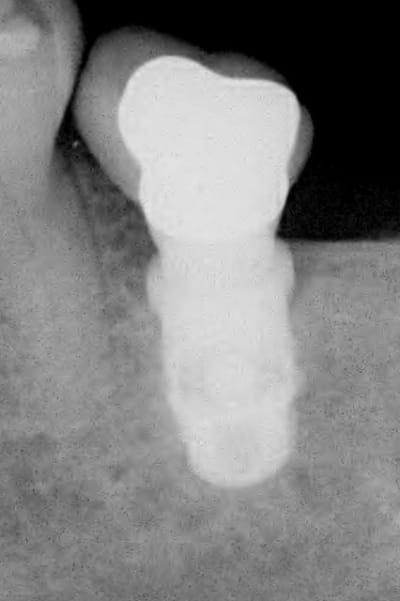

rx à j=0 et j+4 mois

ce qui est surprenant , c'est la présence d'os au niveau du col.

Oui on connait chez Leone mais reproductible sur toute la gamme. C'est qu"est que je dit! Mais nous c'est démontable et indexé. Un vieux cas en rx 5 ans entre les deux rx.